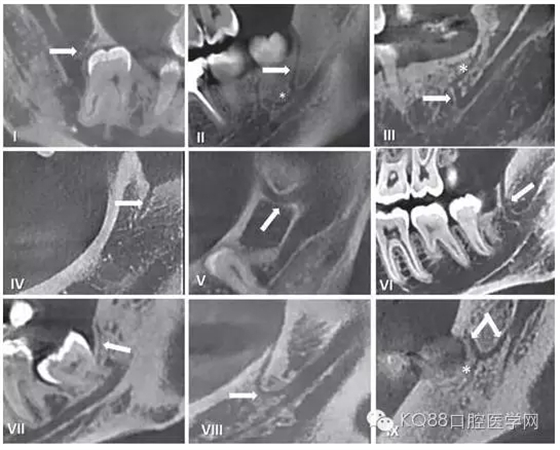

圖五 使用CBCT拍攝到的不同走行的下頜后管

在臨床工作中,個體解剖差異導(dǎo)致像磨牙后管這類的神經(jīng)分叉及神經(jīng)走行的變化,術(shù)前只能通過放射方法檢測。但使用口腔曲面斷層片之類的常規(guī)二維影像學(xué)照片是難以檢查到的。隨著現(xiàn)代醫(yī)學(xué)影像技術(shù)的發(fā)展,出現(xiàn)了計算機斷層掃描(CT)和錐束CT(CBCT),其在口腔醫(yī)學(xué)領(lǐng)域的成功運用使得磨牙后管的術(shù)前影像評估成為可能。精確的捕捉到下頜磨牙后管的解剖走行,需要高分辨率的成像設(shè)備并保證攝像期間患者沒有晃動。下面我們將用幾張CBCT影像圖片為大家圖示說明。